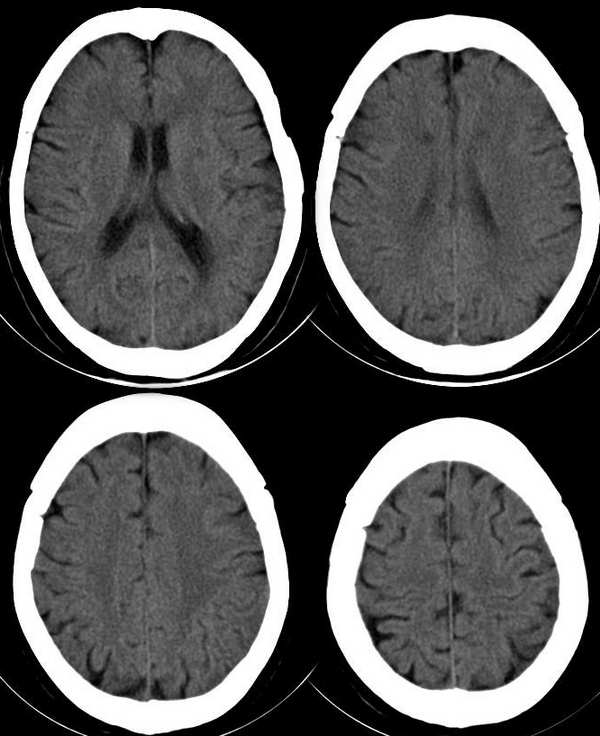

女,76岁,高血压病史二十余年。8小时前出现头晕,呕吐。无神经系统体征

1、左颞叶皮层点状钙化灶,患者年龄较大,多考虑生理性钙化。

2、脑沟裂增宽加深,脑萎缩。